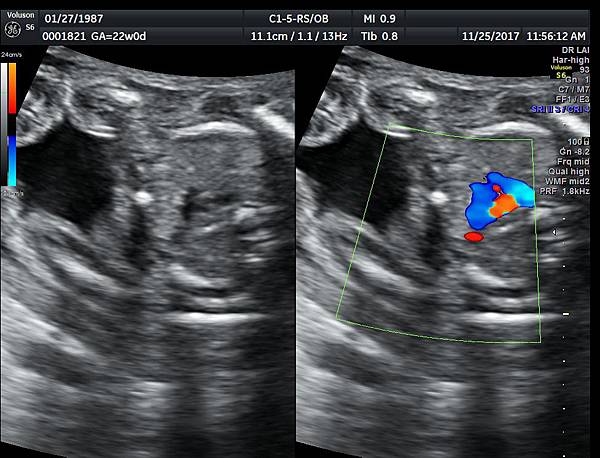

有一對夫妻因為我之前迷走性右側鎖骨下動脈(ARSA)的診斷而選擇孕兒診所,先生告知因為曾經有一個產前被我診斷ARSA的個案在他們醫院出生,他們花很久的時間才證實新生兒有ARSA,他覺得我很厲害,我有點不好意思,其實對專家而言,胎兒時期要診斷ARSA比新生兒容易,原因是胎兒時期超音波下,這條血管可以很清楚的被看到,它是從主動脈出來經過氣管的後面由左側繞到右側(附圖 1.),但是新生兒心臟超音波要看這條血管有困難,因為氣管擋住這條血管,醫師只能靠主動脈的第一個分支(brachiocephalic artery)沒有呈現 y 的特徵(附圖 2.),所謂 y 是brachiocephalic artery正常是會分出兩個分支(附圖 3.4.),一個是right common carotid artery,另一個是right subclavian artery,如果有迷走性右側鎖骨下動脈( ARSA ),就不會有正常的right subclavian artery,所以在新生兒的右頸部就不會看到 y的特徵,新生兒要直接看到迷走性右側鎖骨下動脈( ARSA)這條血管真的要花很多的時間(參考第51篇文章)。